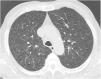

Case reportA 69-year-old man, with history of hypertension and dyslipidemia, was diagnosed with high-grade bladder urothelial carcinoma (pT1). A transurethral resection of the bladder was performed, followed by mensal BCG intravesical instillation in the last 18 months, without major adverse reactions except flu-like symptoms lasting less than 48 h after each dose. Two days after the last instillation, he presented macroscopic hematuria and severe fatigue, sweating and persistent non-productive cough. Eight days later, due to the persistence of symptoms and the appearance of dyspnea and fever, he went to the emergency department. He had no recent sick or tuberculosis contacts. On admission, he was febrile (38.3 °C), hypotensive (89/40 mmHg), in respiratory distress with inspiratory crackles in both lungs. Arterial blood gas analysis showed, in ambient air, hypoxemia [partial pressure of oxygen 63 mmHg) and respiratory alkalosis. Laboratory tests revealed mild anemia (hemoglobin 11.9 g/dL) with normal white blood cell and platelet count, increased levels of C-reactive protein (10.9 mg/dL) and erythrocyte sedimentation rate (57 mm/h), acute kidney injury [serum creatinine (sCr) 2.35 mg/dl], hematuria, leukocyturia and proteinuria. Serological tests were negative for hepatitis B and C and human immunodeficiency virus. Markers of immune-mediated disease (antinuclear, antineutrophil cytoplasmic, antiglomerular basement membrane and anti-streptolysin O antibodies) were all negative. Serum immunoglobulins and complement levels were normal. The chest radiography showed a bilateral reticulonodular infiltrate (Fig. 1) and the thoracic computed tomography (CT) demonstrated a diffuse pulmonary micronodulation, in a miliary pattern (Fig. 2). Renal ultrasonography revealed normal-sized kidneys with a reduced corticomedullary differentiation. Specimens for microbiological exam were collected and empirical broad-spectrum antibiotic treatment was started. On the fifth day of treatment, both fever and acute respiratory failure persisted, lung opacities were unmodified and renal function worsened (sCr 3.52 mg/dL). Multiple cultures of sputum, urine and blood were negative for both bacteria and mycobacteria, including polymerase chain reaction (PCR). A bronchoscopy with bronchoalveolar lavage (BAL) was performed which revealed a prevalence of lymphocytes (48.2%) and an elevated CD4/CD8 ratio (11), absence of malignant cells and bacteriological and mycobacteriological exams were negative. Due to the lack of clinical and imagiological improvement, the diagnosis of disseminated BCG infection was suggested and empiric anti-tuberculosis treatment (ATT) [isoniazid 300 mg, rifampin 600 mg and ethambutol 1200 mg; once daily] associated with a corticosteroid (prednisolone 60 mg once daily) was started and, few days later, patient’s clinical condition improved, with sustained apyrexia, resolution of acute respiratory failure and slow but steady recovery of renal function. He was discharged in good general condition and continued ATT for 6 months. Steroids were discontinued tapering down the dosage for 5 months. A high-resolution CT scan of thorax, performed 6 months after discharge, showed almost complete resolution of the lung opacities with a reduction in the number and size of bilateral pulmonary nodules (Fig. 3) and kidney function was fully recovered (sCr 0.86 mg/dL). BCG immunotherapy was discontinued. No sign of relapse was observed after one year of follow-up.

Pulmonary involvement is very rare and can present as hypersensitivity or mycobacterial pneumonia. Hypersensitivity is usually characterized by an interstitial pattern in chest x-ray and lymphocytosis on BAL.12 Miliary pattern nodules in lung parenchyma is rarely reported in the literature. An extensive and systematic review of the literature, retrieved 26 published cases11–36 (Table 1) which provide a comprehensive clinical, radiological and microbiological information of miliary tuberculosis caused by disseminated BCG infection in adults treated with intravesical BCG immunotherapy.